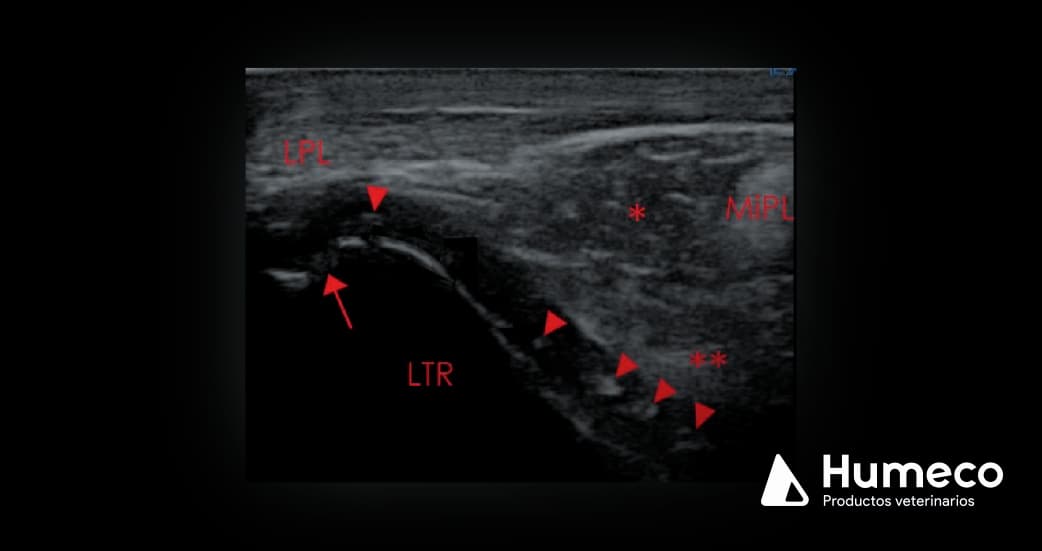

El cartílago articular normal es anecoico (negro) y regular, mientras que el cartílago afectado suele verse heterogéneo en ecografía, y puede contener regiones más fuertemente ecoicas (puntas de flecha, imagen 1,2).

El hueso subcondral subyacente puede ser irregular (flecha, imagen 1).

Imagen 1: Imagen transversal de la cresta troclear lateral (LTR) del fémur de un caballo Warmblood con OCD fermoropatelar. La parte lateral está a la derecha de la imagen. LPL = ligamento rotuliano lateral; MiPL = ligamento rotuliano medio, *= regiones moderadamente hiperecoicas dentro del cartílago articular, consistentes con OCD.